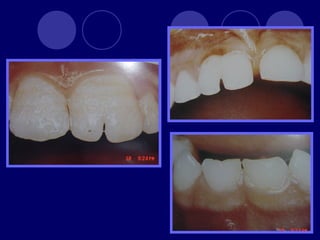

• 45.

AMELOGENESIS IMPERFECTA  Hipoplásico: Zonas ausentes de esmalte  Afecta más a caras vestibulares  Esmalte: blanco amarillento y marrón claro, consistencia dura, fosas y surcos oscuras, delgado  Hipocalcificado:  Cualitativo  Esmalte frágil, fácil de desprender  Rx: falta de contacto entre dentina, esmalte  Hipomaduro:  Disminución en el contenido mineral  Esmalte blando y rugoso, veteado de blanco a marrón (esmalte en copos de nieve)  Más frecuente en caras vestibulares y dientes superiores